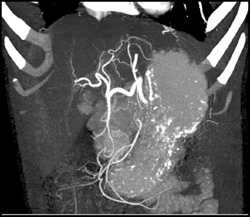

Cirrhosis With Varices